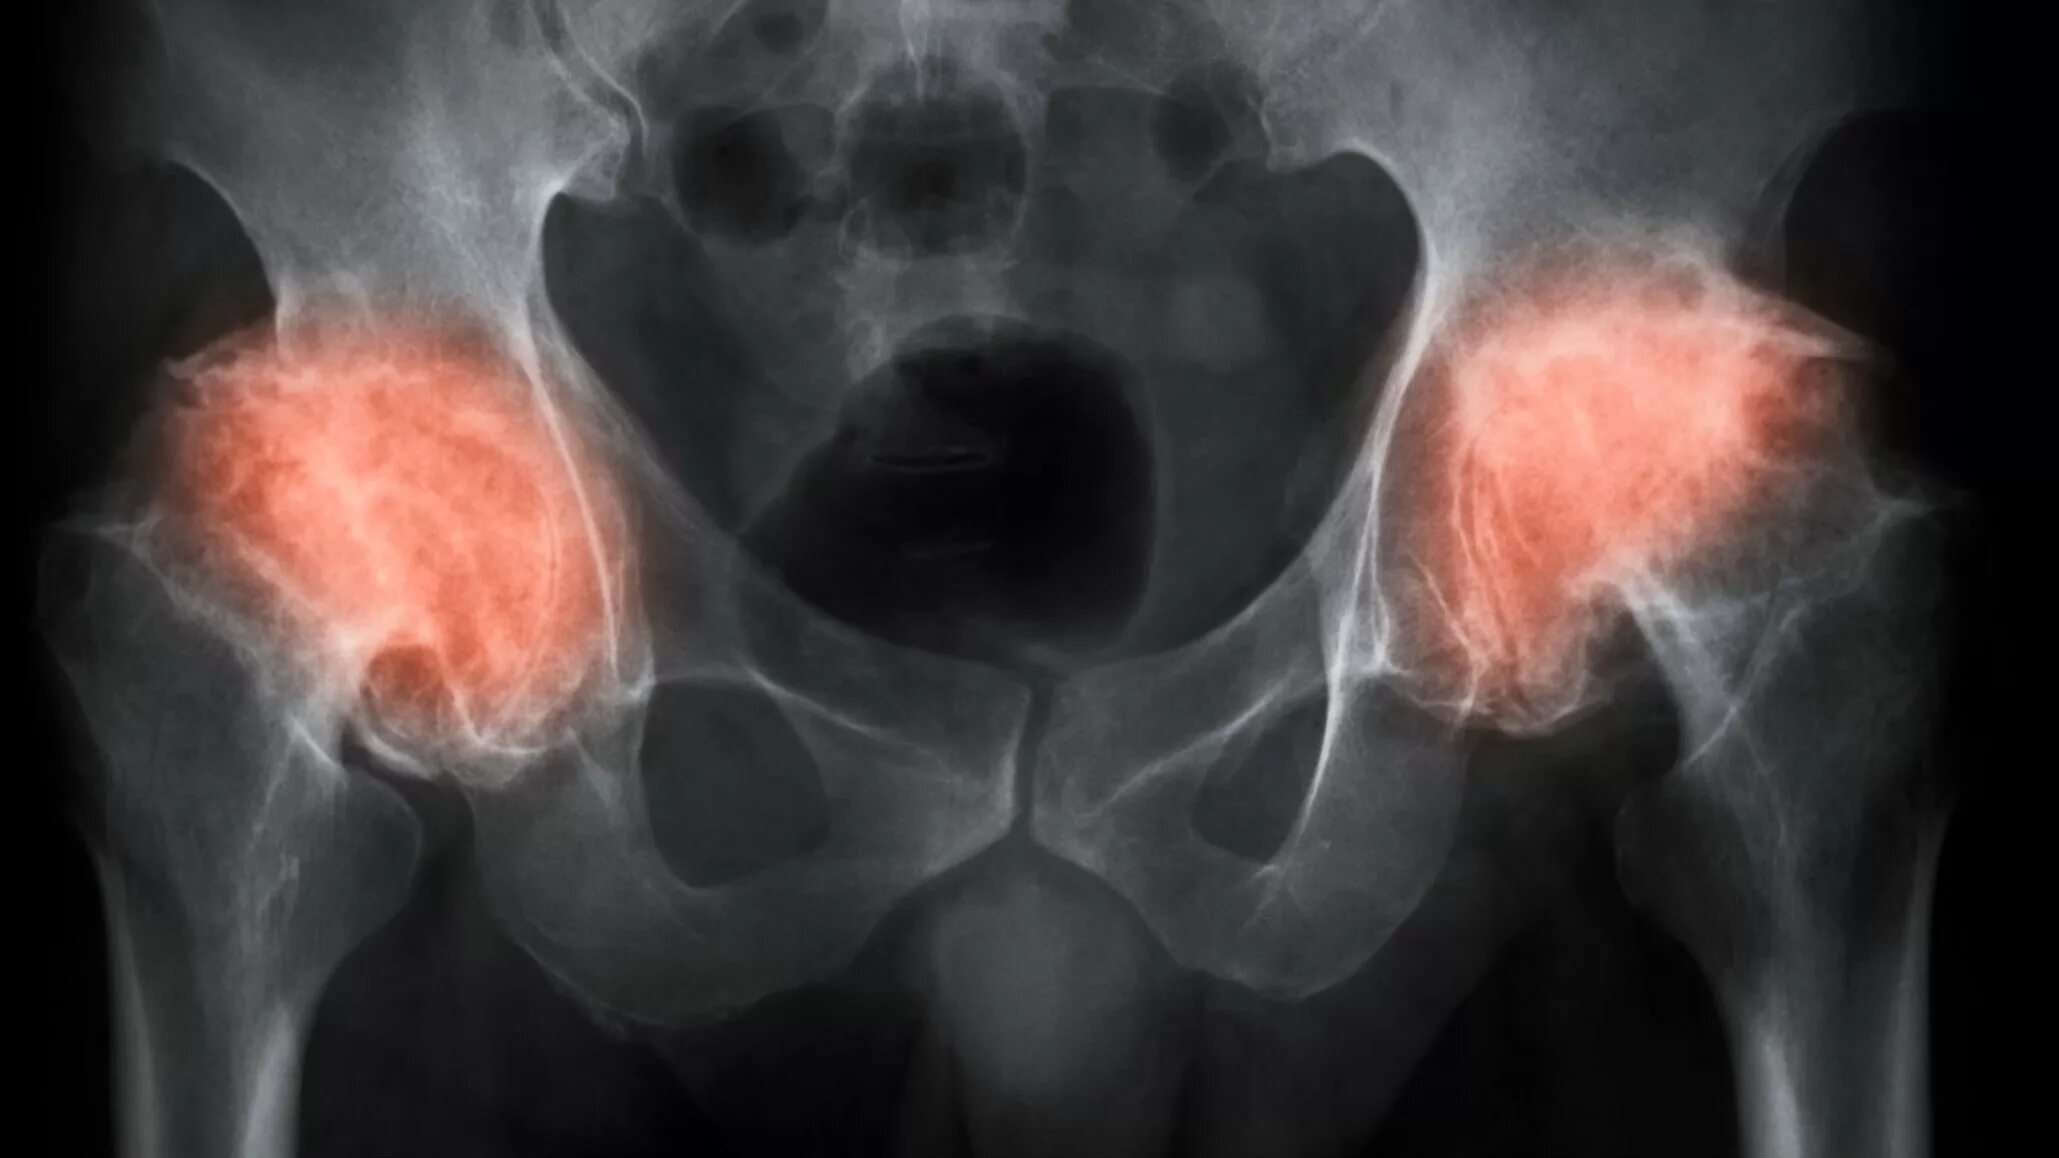

Коксартроз тазобедренного 1 стадии